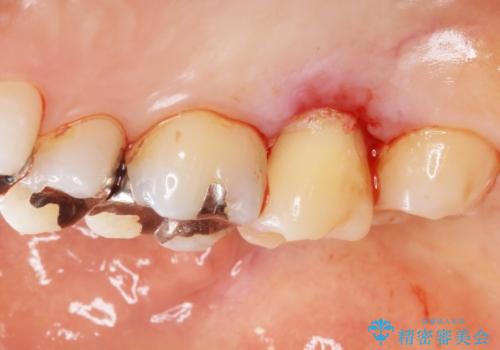

精査したところ、右上の奥歯(右上7)はう蝕が深く骨吸収も進行しており保存不可能な状態でした。

金属アレルギーの疑いがあり、インプラントも避けたいとの患者様のご希望により、親知らずを移植することにしました。

移植がうまくいかない可能性を考慮し、ブリッジもできるよう隣の親知らず(右上8)は残し、反対側の親知らず(左上8)を移植しました。